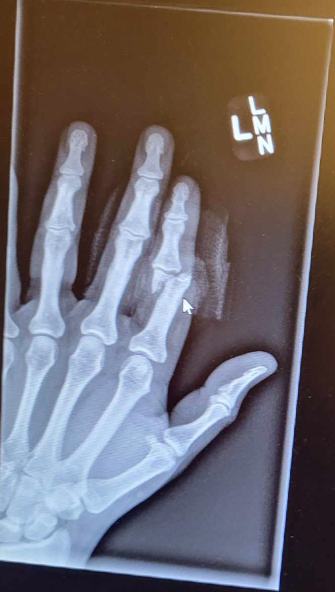

Just don't do this!

A buddy just sent me this. This is 2 weeks post surgery. He got his finger in the way of a splitter helping a buddy split wood.

That is a pin holding the bones together to heal. It will be removed once healed.

When it first happened he captioned these photos with, "apparently I'm not as good with this whole wood splitting thing as you are". LOL He said the finger was just hanging.